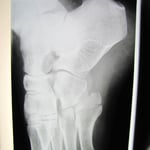

〇右前腕骨骨折(スミス骨折)

自転車で転倒し手をつき手首を骨折しました。

病院でレントゲン検査の結果、3か所の骨折が認められました。

後日手術の予定が組まれ,全身麻酔下で行うことを聞かされた時に非常に困惑し、セカンドオピニオンとして手の専門外科に相談に行かれました。

ここでも手術療法が妥当だと日程を組むことになってしまいました。

手術をしないで治ることはできないかとインターネットで調べ当院を知り相談に来られました。

今回事情を聴き、整形外科の先生と相談をし当院で処置と経過観察をすることになりました。

整骨院の従来の固定法である副木(シャーレ)と包帯を駆使して患者さんに負担の少ない固定をしました。

毎日 固定具を外し患部の浮腫の除去、血行維持、清拭、超音波治療を行います。固定具に不自由があれば

修正をしました。 このように毎日患者さんに触れ、不安を聞くことにより自律神経も安定し良い結果につながるのです。

経過は非常に良好で転移(骨のずれ)もなく約2か月で薬剤師の仕事に復帰されました。